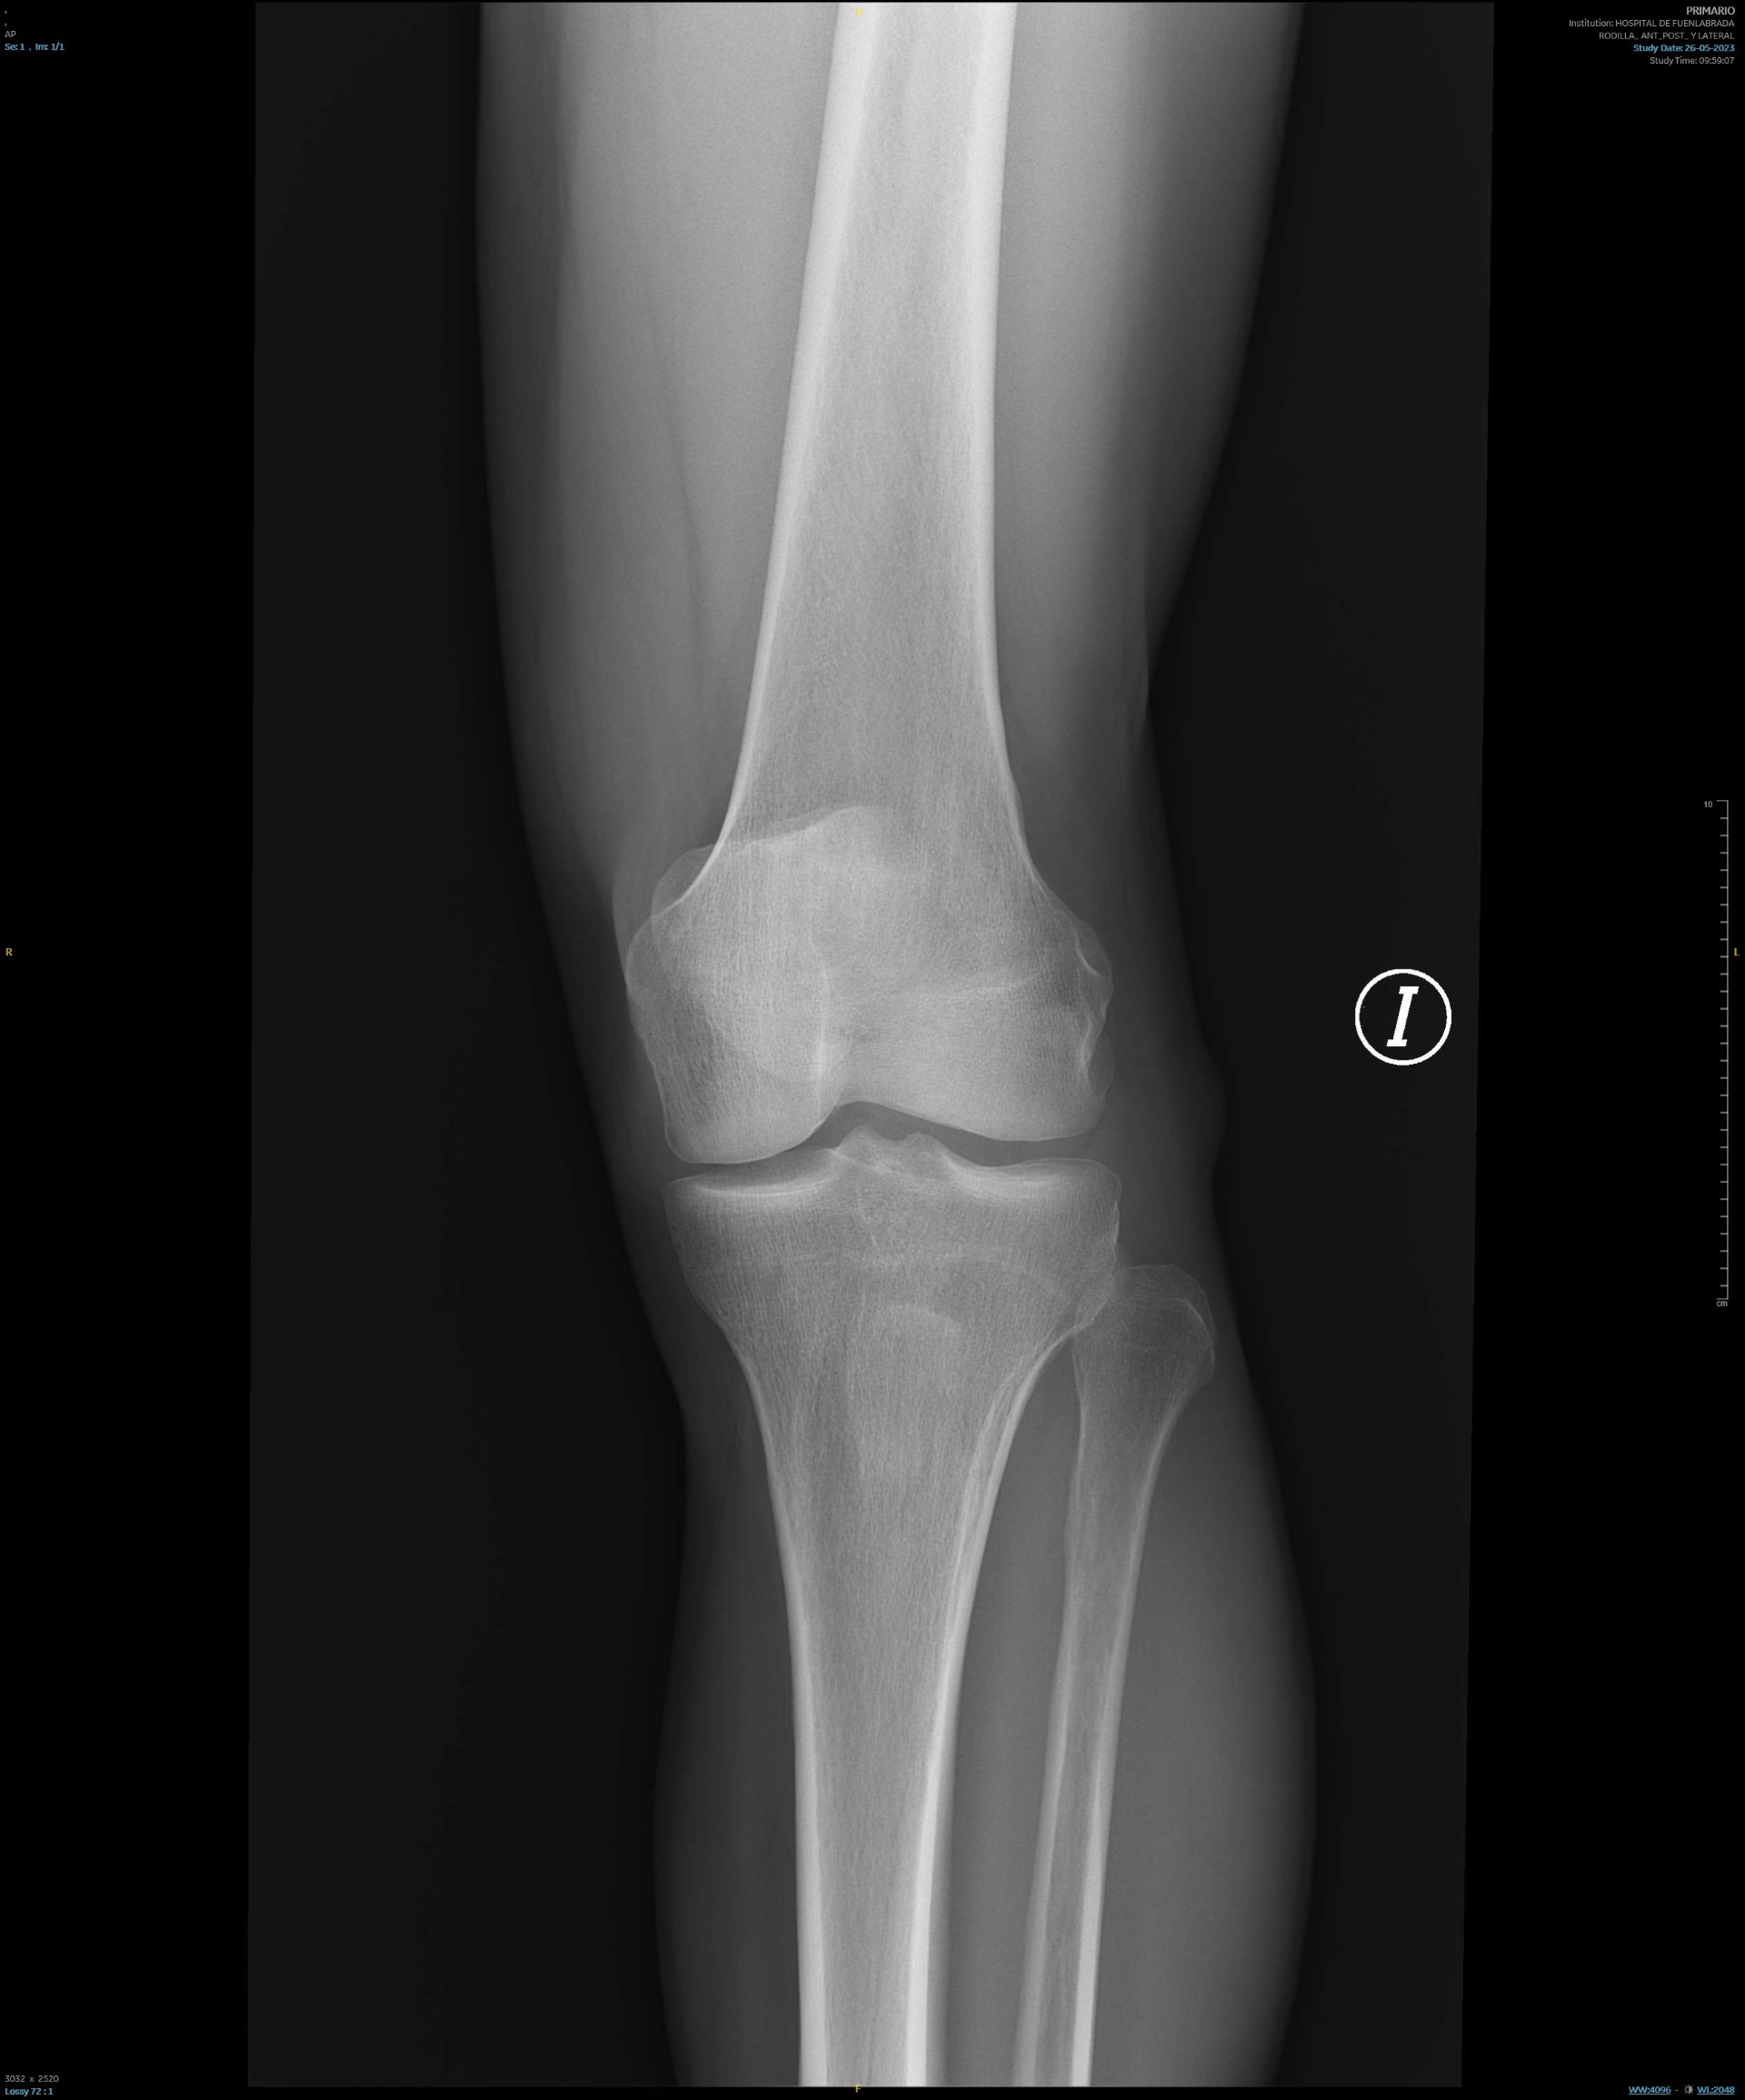

Rx de rodilla: sin alteraciones.

RMN: Lesión nodular en compartimento externo sugiere quiste poplíteo o bursitis de unos 2,5 cm.